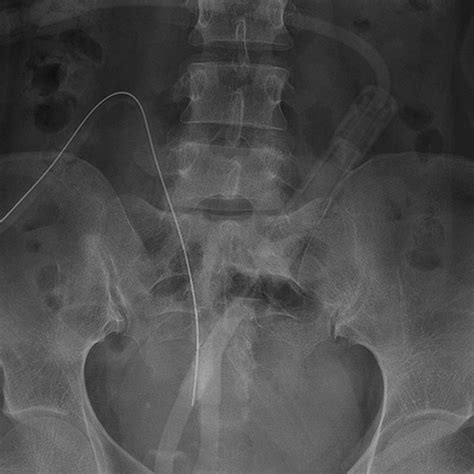

On the day of the Pd Catheter Placement, the procedure is performed in a sterile operating room environment. After anesthesia is administered—which may be local, regional, or general depending on the surgical approach—the surgeon creates a small incision. The catheter is carefully threaded into the peritoneal cavity, typically targeting the Pouch of Douglas, which is the lowest point in the abdominal cavity to ensure gravity-assisted drainage.

Once positioned, the catheter is anchored with internal cuffs. These cuffs are critical because they encourage tissue ingrowth, which effectively seals the tract and prevents bacteria from traveling along the outside of the tube into the peritoneal space. The tube is then tunneled subcutaneously before emerging at the exit site. This subcutaneous tunnel acts as an additional barrier against infection.